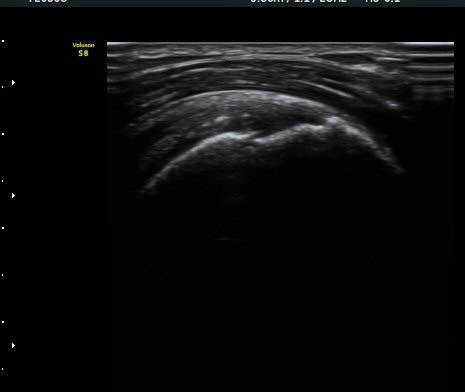

¿Í ¼Ò°áÀý »óºÎ(±×¸² 4)¿¡¼­ ƯÀÌ ¼Ò°ßÀ» º¸ÀÌÁö ¾Ê´Â´Ù.

À­ÆÈÀ» ³»È¸Àü, ³»ÀüÇÑ »óÅ¿¡¼­ ±Ø»ó°Ç Á¾´Ü¸é°Ë»ç¿¡¼­ ±Ø»ó°Ç ³»Ãø¿¡¼­ ƯÀÌ ¼Ò°ßÀ» º¸ÀÌÁö

¾ÊÀ¸³ª(±×¸² 5) ±Ø»ó°Ç ¿ÜÃø¿¡¼­ ´ë°áÀý ÇÇÁú°ñ ¿¬°á¼º ¼Ò½ÇÀ» º¸ÀδÙ(±×¸² 6). ±ØÇ졂 Á¾´Ü¸é